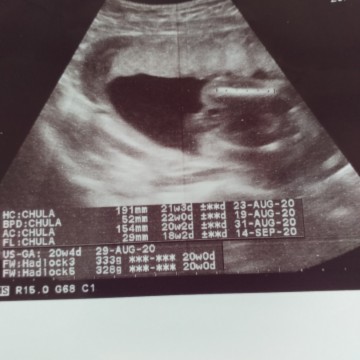

ซาวด์ตอน19+3 ค่ะ